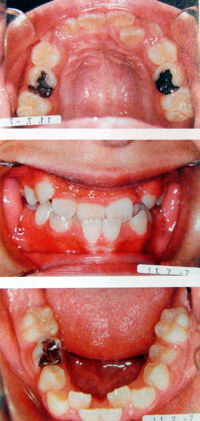

子供の例

狭く細長い歯並び

舌が収まりきれず、気道を圧迫し、いびきや無呼吸症候群の原因となります。

小さい顎には装置を使用します。1日10時間程度、自宅で装置を使い、歯を抜かずに本来の位置まで顎を成長させる治療です。